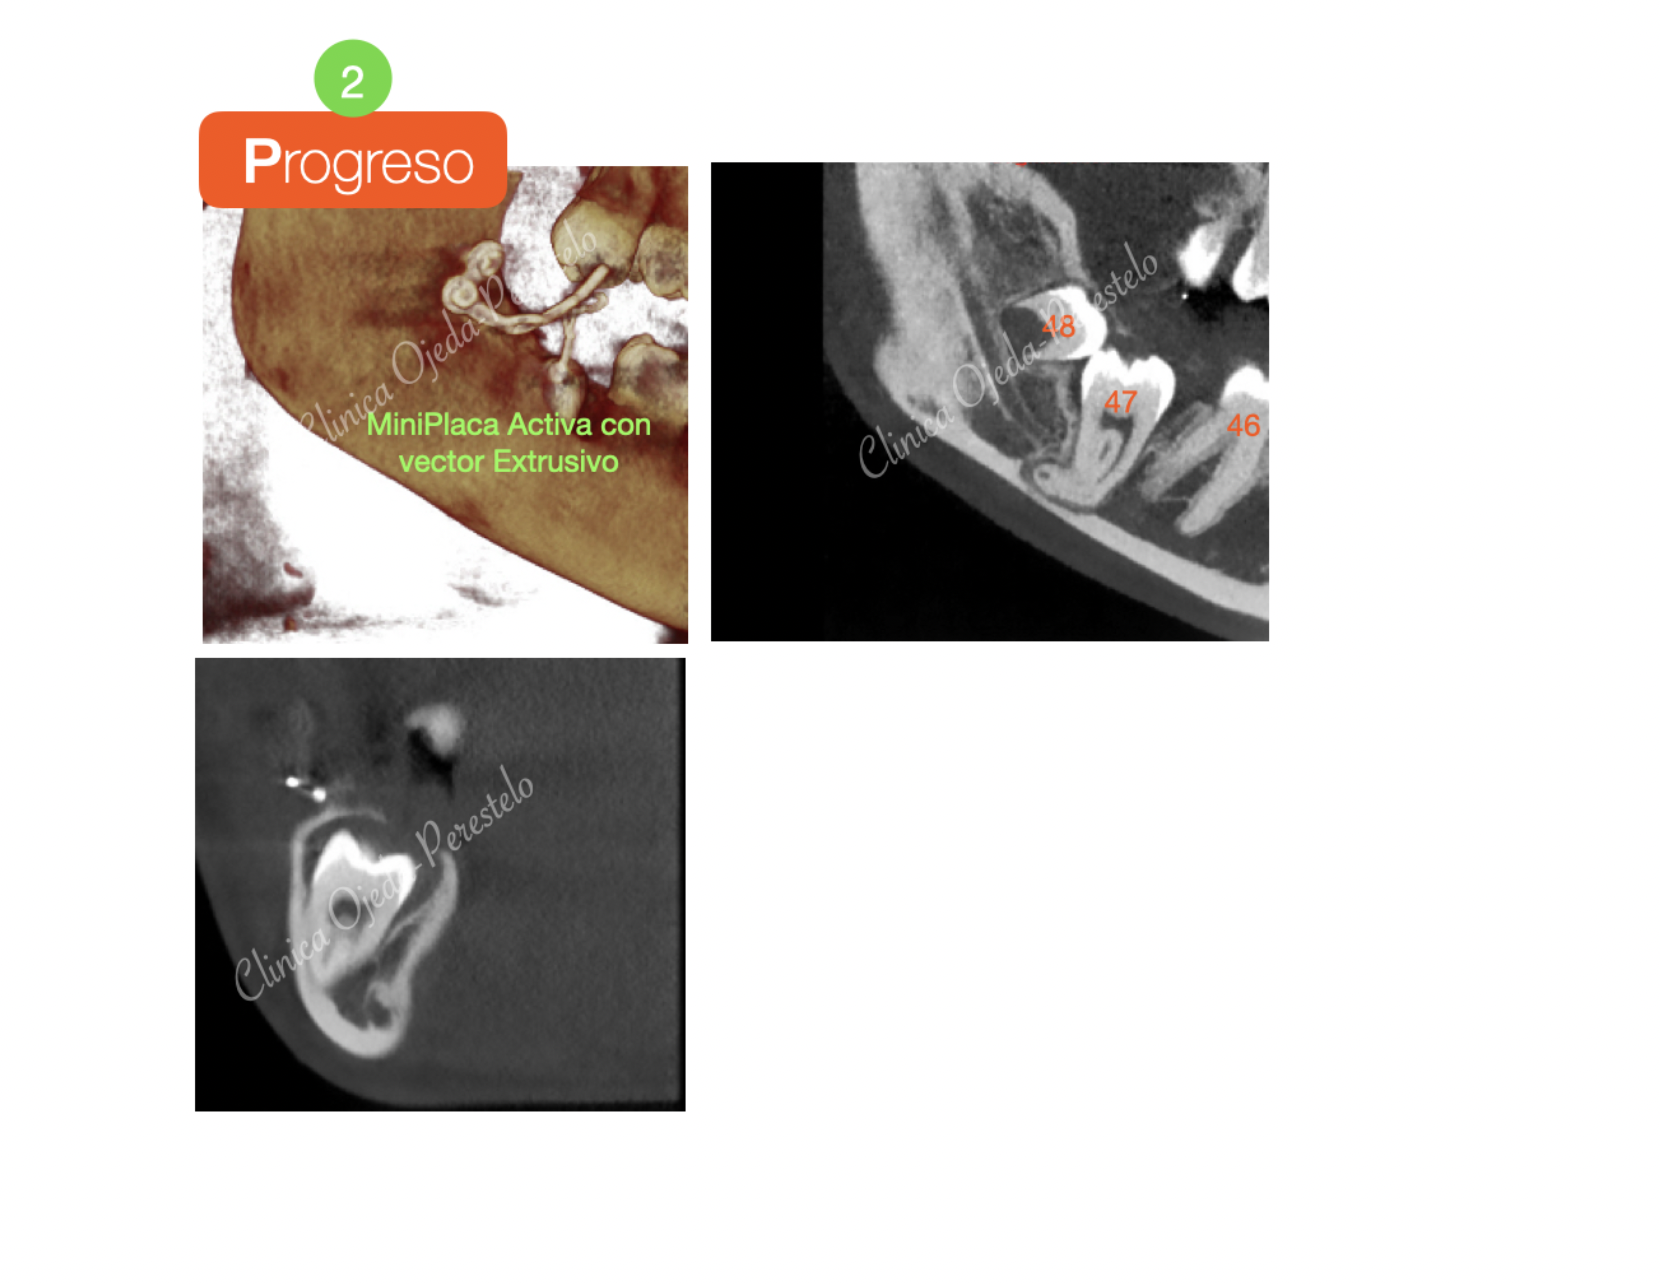

Podemos observar cómo hemos podido reconducir la pieza 47 al plano de oclusión de manera exitosa en un plazo de 15 meses tras la colocación de una Miniplaca semiactiva con tracción ortodoncia continuada. Actualmente la paciente está en fase de comenzar su tratamiento de Ortodoncia Plástica a efectos de poder mejorar la alineación, nivelación y la articulación de sus piezas dentarias.